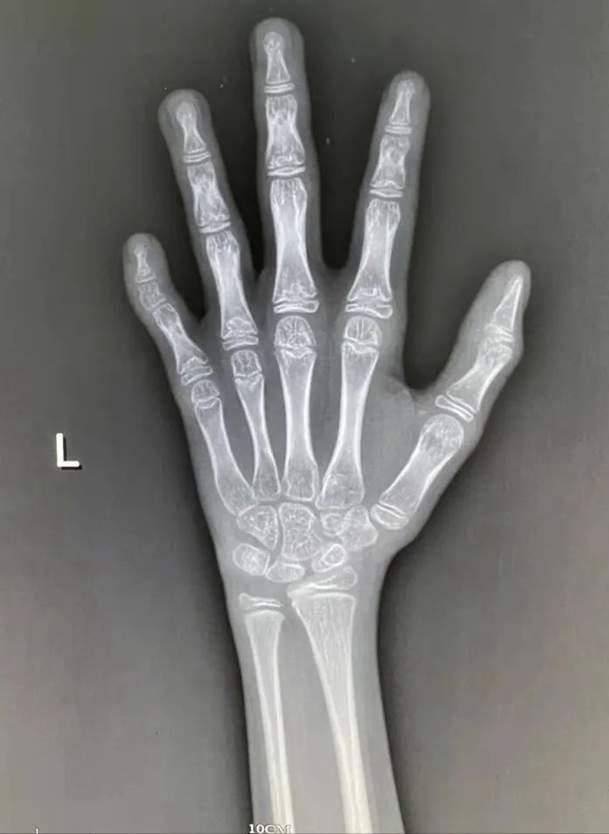

为什么每年要带孩子去拍骨龄片呢?

拍骨龄片可以帮助医生确定孩子的身体发育状况。拍骨龄片可以检测孩子的身高、体重、骨密度等,从而可以判断孩子的身体是否正常发育。如果发现孩子的身体发育出现异常,及时发现并采取措施,可以有效预防和治疗疾病。帮助家长了解孩子的身体发育情况,更好地指导孩子的生活习惯,为孩子的健康成长提供有效的保障。